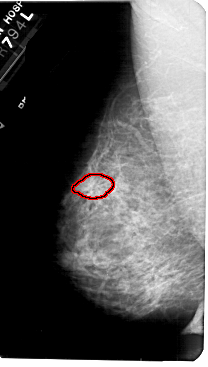

A_1777_1.LEFT_CC

LEFT_CC LINES 4966 PIXELS_PER_LINE 2911 BITS_PER_PIXEL 12 RESOLUTION 43.5 OVERLAY

FILE: A_1777_1.LEFT_CC.OVERLAY

TOTAL_ABNORMALITIES 1

ABNORMALITY 1

LESION_TYPE MASS SHAPE ARCHITECTURAL_DISTORTION MARGINS ILL_DEFINED

ASSESSMENT 4

SUBTLETY 2

PATHOLOGY BENIGN

TOTAL_OUTLINES 1

BOUNDARY